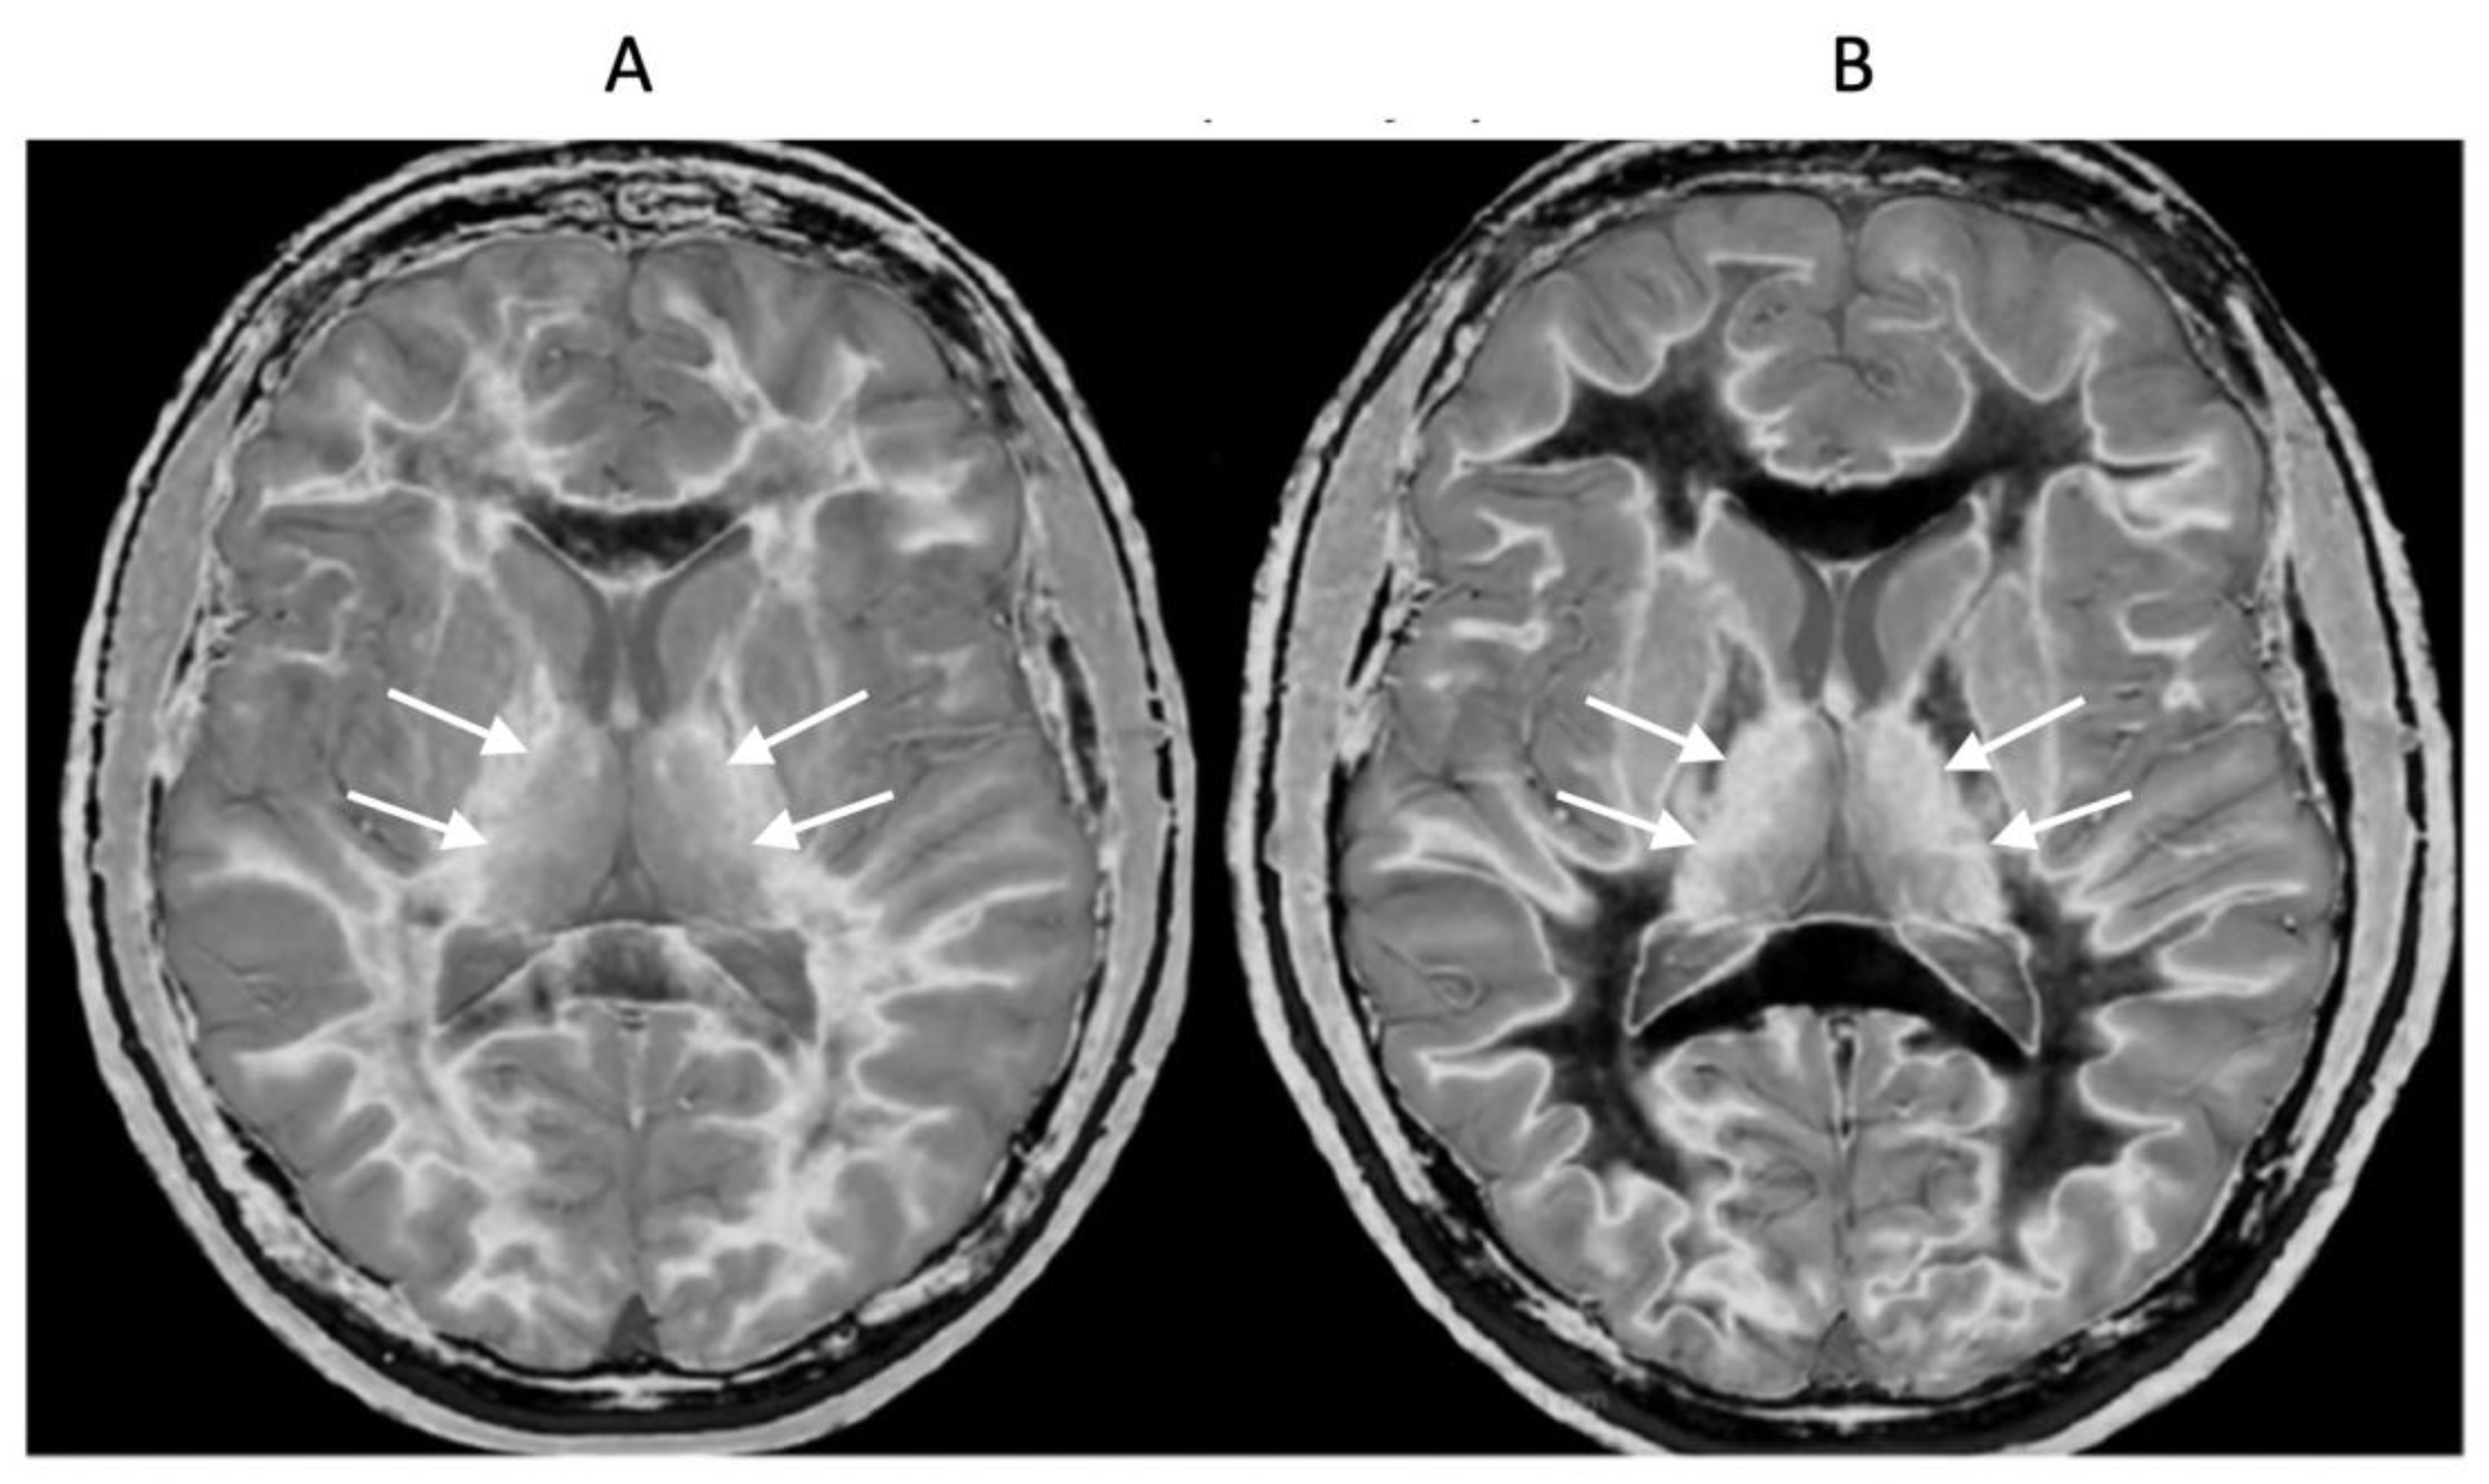

Figure 12.

18-year-old patient with mTBI 21h (A) and 64h (B) post injury imaged with the same narrow mD dSIR (T1-BLAIR) sequence. In (A) the patient shows a whiteout sign (grade 4 out of 5) with high signal in most of the white matter in the cerebral hemispheres except for the anterior and posterior central corpus callosum. The posterior limb of the internal capsule is high signal. The thalami show low internal contrast from medial to lateral (arrows on lateral margins of the thalami). There is also low external contrast between the lateral margins of the thalami and the adjacent posterior limbs of the internal capsule. On the follow up examination at 64h (B) the whiteout sign has resolved with low signal now in the white matter including the posterior limbs of the internal capsule (except for the corticospinal tracts). The thalami now show high internal contrast from medial to lateral (arrows on lateral margins of the thalamus) which is the normal appearance at this age. There is now also very high external contrast between the lateral margin of the thalamus and the adjacent posterior limb of the internal capsule. Image (A) shows the grayout sign which is a reduction in the high contrast between the medial and lateral gray matter of the thalamus. The high contrast is restored in (B). No abnormality was seen on the corresponding T2-FLAIR images obtained at both time points.